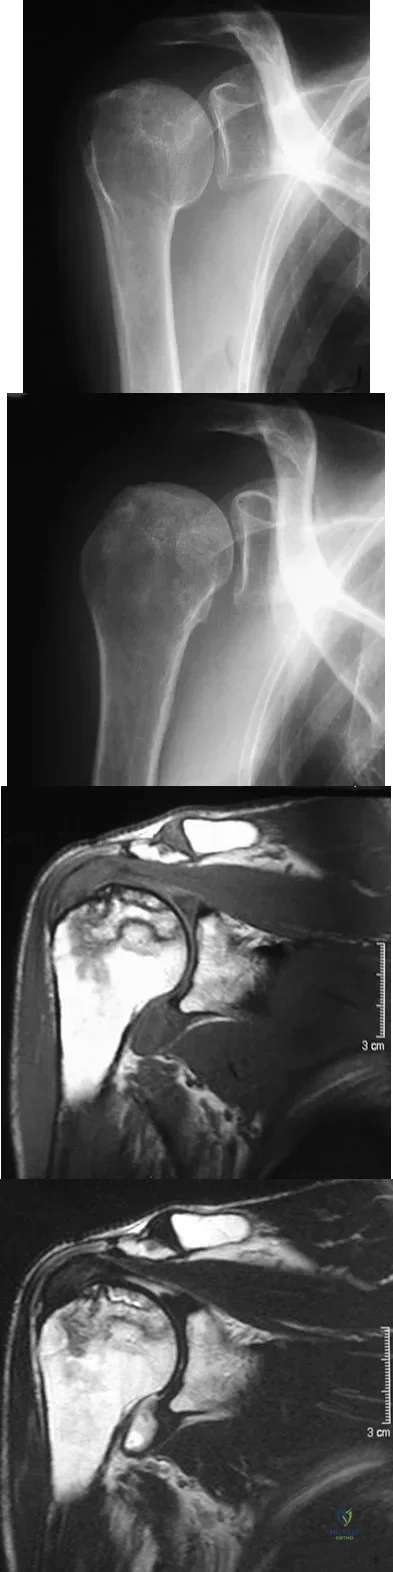

A 58-year-old woman with a history of severe asthma and long-term prednisone use reports a progression of chronic shoulder pain for the past 6 months. Radiographs and MRI scans are shown in Figures 30a through 30d. What is the most likely diagnosis?

Explanation